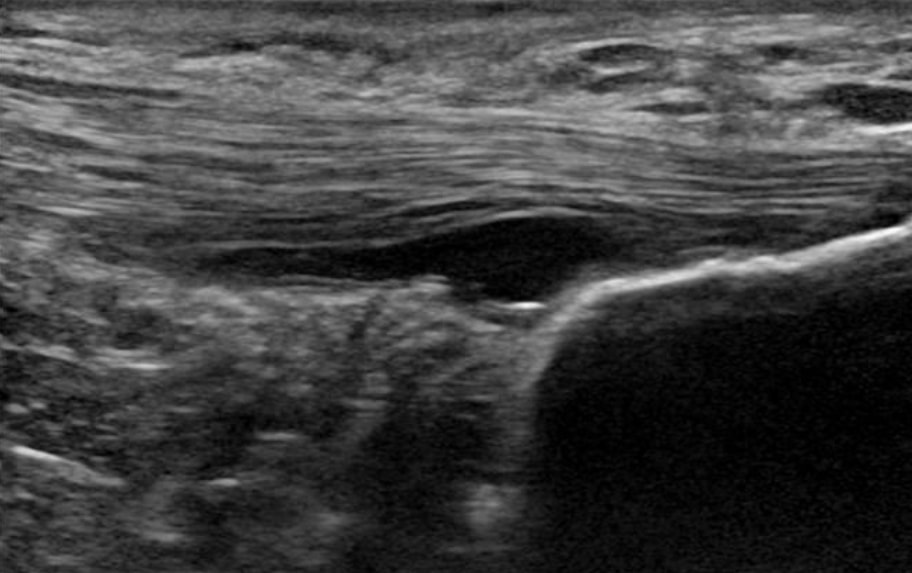

6. Un tendon pathologique est mieux structuré qu'un tendon normal(Docking et al. 2015). Cela signifie que nous pouvons charger ces tendons parce que nous avons des charges de bons tissus. Les thérapies pour la pathologie du tendon ne sont pas nécessaires, car nous ne pouvons de toute façon pas modifier la structure de la partie pathologique. C'est pour cette raison que Docking et ses collègues ont inventé la citation "Traiter le beignet, pas le trou" - en d'autres termes, se concentrer sur la structure saine et non sur la partie pathologique.

Un tendon pathologique a une plus grande structure qu'un tendon normal (Docking et al. 2015)